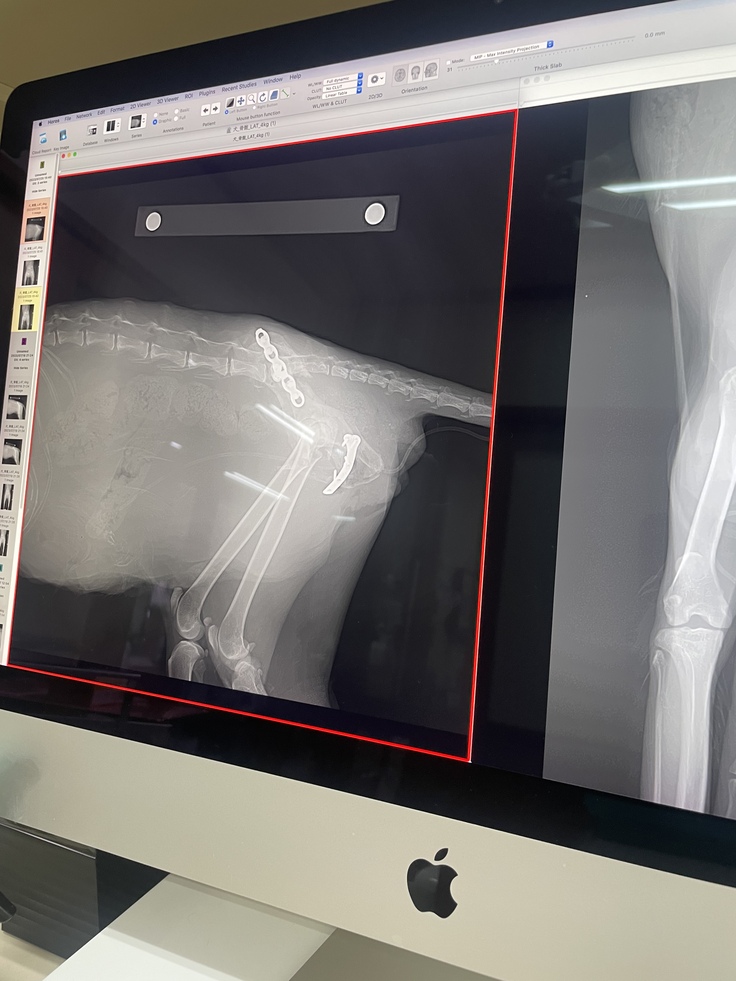

7/18日手術決行

初診を行って貰った病院の方で手術が行える病院を紹介して頂き地元帯広から車で3時間ほど離れた旭川の病院の方で手術を行って貰いました。

野良猫ちゃん大歓迎という事で手術費用も安くできるよう手配して頂き大変助かりました。ありがとうございます。

手術後レントゲン